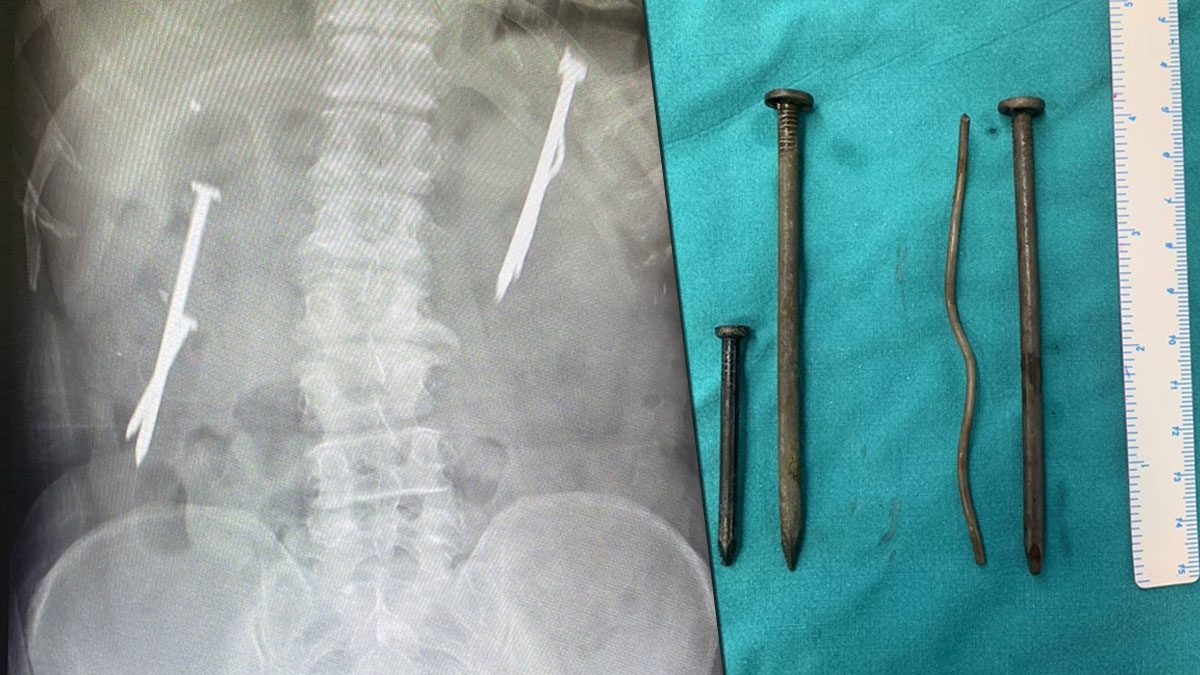

2. เสกตะปูเข้าท้อง (Spell out tghe nails)

“เสกตะปูเข้าท้อง” หรือ “Spell out the nails” เป็นกระบวนการทางเวทมนตร์หรือศาสตร์ผสมผสานที่มักถูกนำมาใช้เพื่อปกป้องหรือสาปแช่งบุคคลหรือสิ่งของ โดยการใช้ตะปูหรือเข็มหรือวัตถุอื่นๆ ที่เกี่ยวข้องกับตำแหน่งที่สำคัญในร่างกายของผู้เป็นเป้าหมาย มักมีความเชื่อว่าการสาปแช่งหรือป้องกันสามารถทำได้โดยการเขียนคำสมัครใจหรือเวทมนตร์บางประเภทลงบนตะปูหรือวัตถุ และทำให้ตะปูหรือวัตถุนั้นเป็นอารามของพลังเวทมนตร์